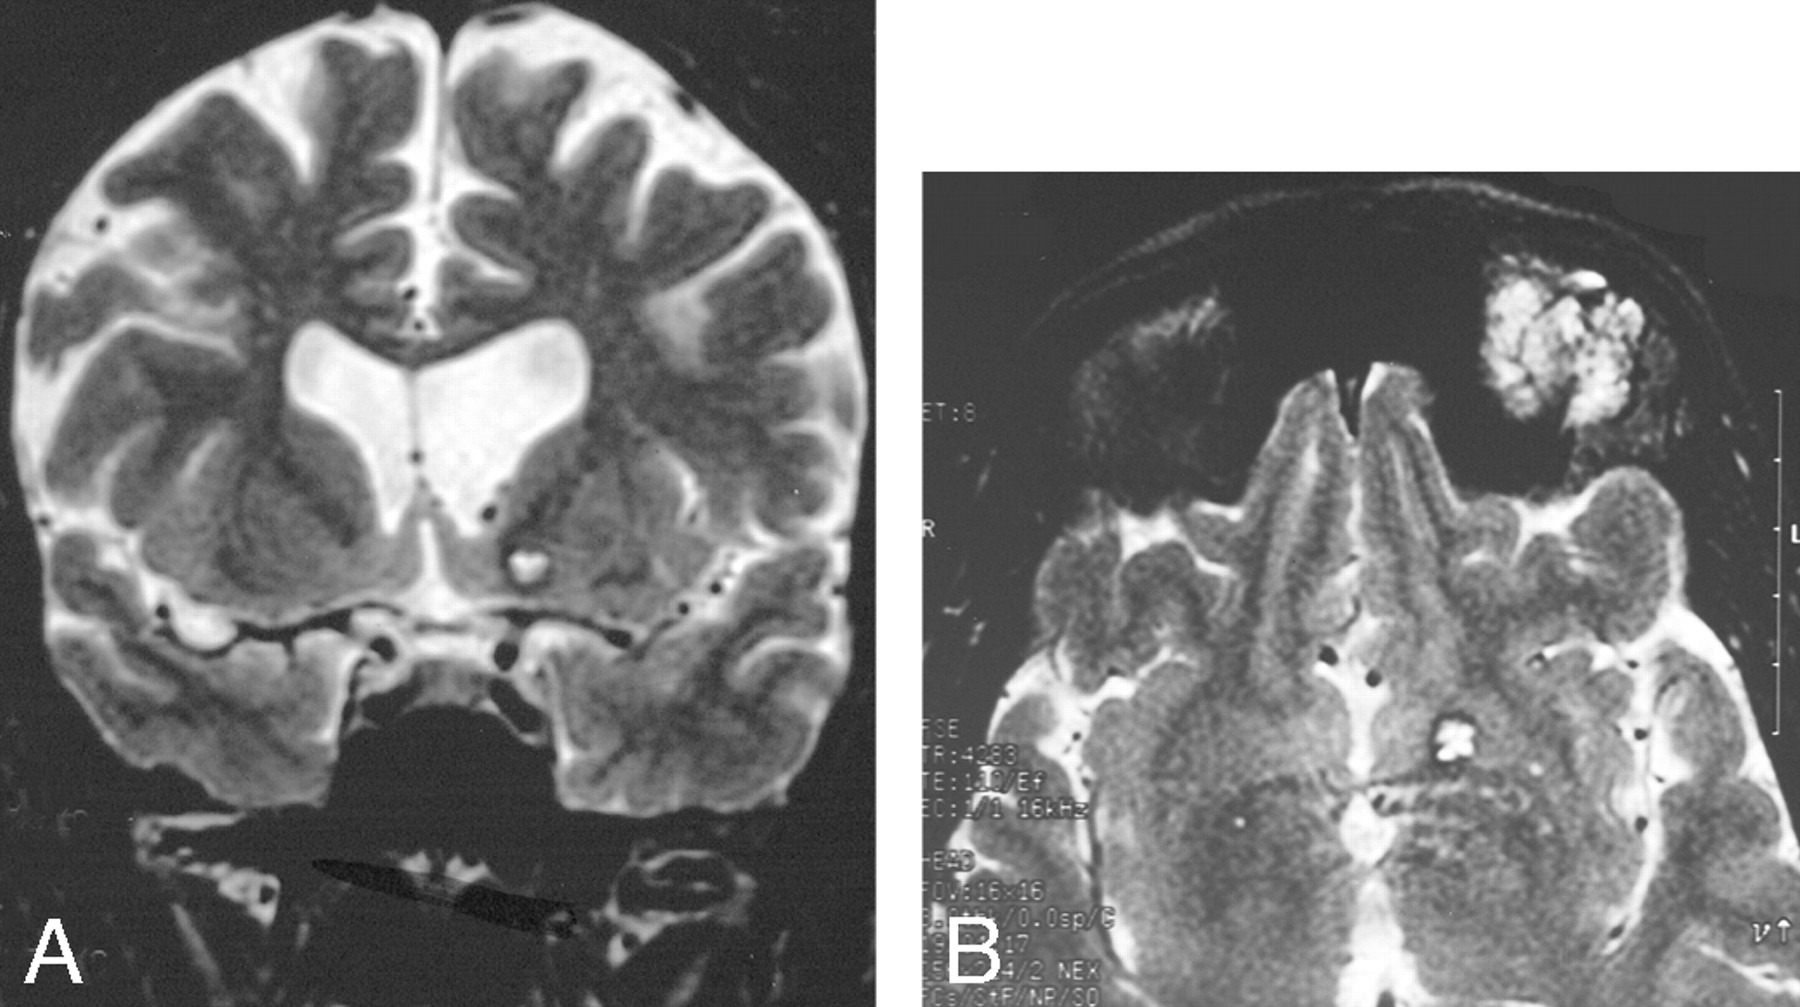

A and B, Cavernoma-like lesion in a patient with a left orbital lymphatic malformation.

A, Coronal T2-weighted MR imaging shows a focal T2-hyperintense area in the left basal ganglia, associated with ventricular dilation.

B, Axial image showing the orbital and basal ganglia lesions.